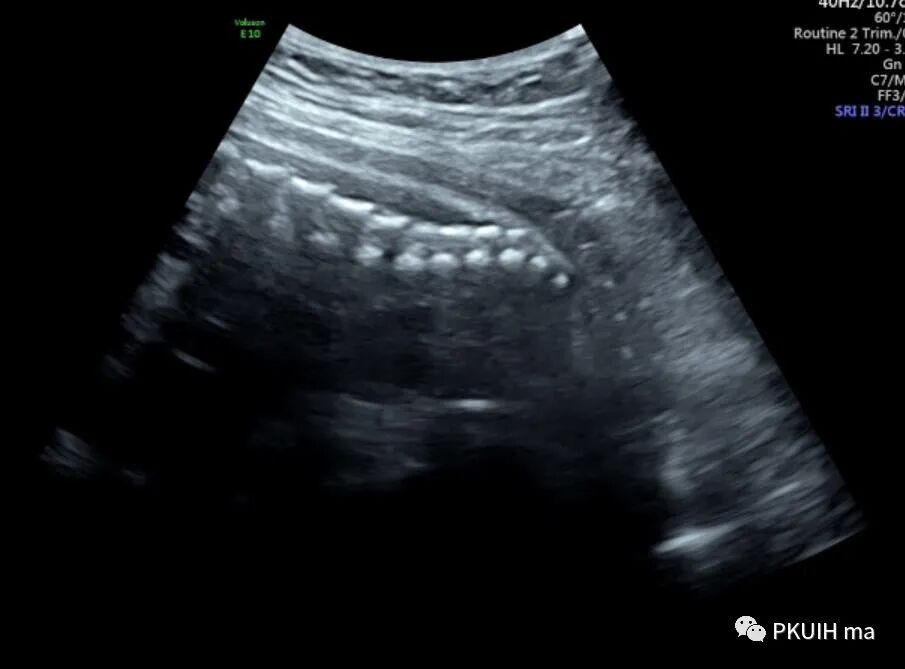

超声显示外生殖器为女性特征,肛门前方见囊性回声,冠状切面显示囊性回声延至会阴处

囊性回声似呈葫芦状,下方大,上方小